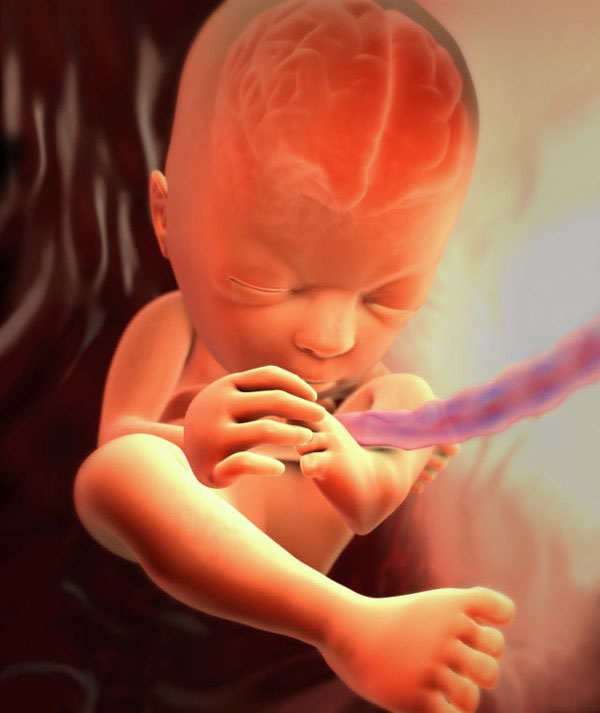

Фото плода на 27 неделе беременности (возраст плода 25 недель)

На 27-й неделе плод уже напоминает новорожденного. У него пропорционально развито тело, четко оформлены черты лица, появились волосы, брови и ресницы. В случае преждевременных родов на этом сроке у малыша высокие шансы на выживание – 85%. Однако для этого ему необходимо находиться в специальном кувезе. При должном уходе малыш сможет не только выжить, но и догнать в развитии своих сверстников. К сожалению, у недоношенных детей существует повышенный риск инвалидности.

Ориентировочные размеры ребенка в данный период выглядят следующим образом: длина составляет 35-37 см, ширина грудной клетки – 69,1 мм, окружность живота – 70,5 мм, а диаметр головы – 67,9 мм. Вес малыша в это время колеблется от 1 до 1,2 кг.